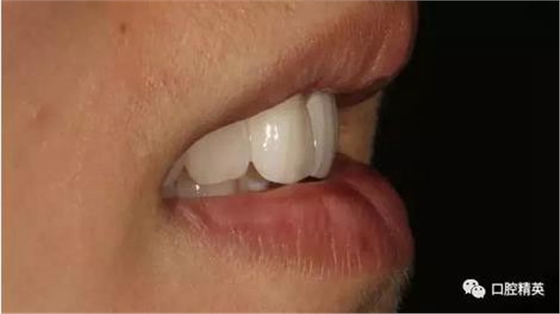

口內(nèi)正側(cè)位及切端特寫(xiě)

從側(cè)位照可看出遠(yuǎn)中切角略有回收